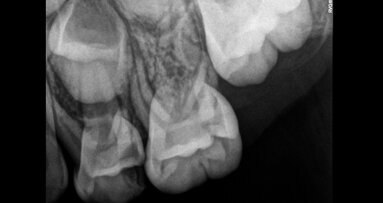

צילומי רנטגן, או הדמיית רנטגן, הם עזר אבחוני הכרחי ברפואת שיניים שכן הם מאפשרים זיהוי ...